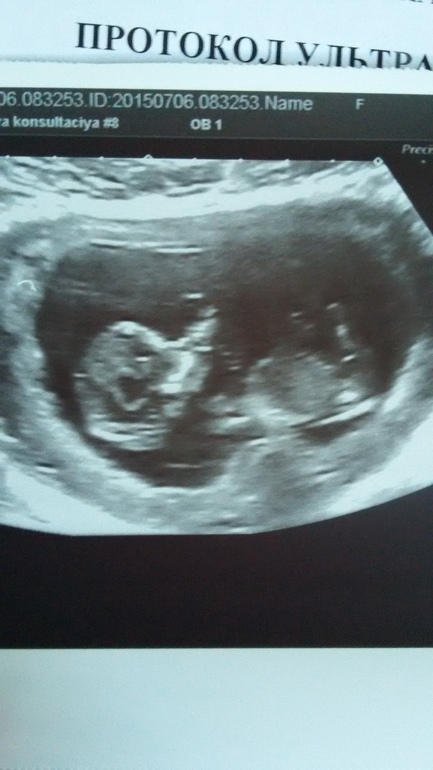

Первый скрининг!

Ой девочки так здорово увидеть свое маленькое чудо!) И так страшно ждать результатов! Но я наледи все отлично :) по уиз все хорошо) мы уже большие совсем))

Поздравляю вас!!!! =)))) Я вчера тоже ходила на первый скрининг, тоже столько впечатлений))))))) Не верится даже, ровно месяц назад делала узи — там еще была такая .. ммм ... какашечка непонятная малюсенькая)))) А вчера уже целый настоящий огромный человек с настоящими руками, ногами, головой=))))))) И мозгом как у взрослого, лицом... Вообще не верится, как за такой короткий срок всё так выросло))))))) (Вот практически такой же как у вас). Мужу показала, тоже не поверил))) Завидует теперь, что я одна ходила без него, он работал. И при чём еще так классно вышло, у них буквально на днях повесили огромную плазму, лежишь и смотришь, как он там ручками машет)))